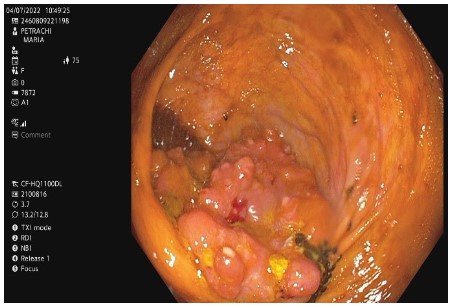

Figure 2: Haematoxylin-eosin staining (magnification, 5x). Detail image showing normal colon mucosa (bottom right) and colon adenocarcinoma with tubular, villous architecture and lympho-plasmocyte inflammatory infiltrate, with tendency to abscess.

Anatomopathological exam of the tumoral mass revealed ulcerated low-grade NOS (Not Otherwise Specified) colon adenocarcinoma (G1), invading thickness of submucosa and muscularis, localised up to the level of subserosa, without affecting serosa (Figure 2).